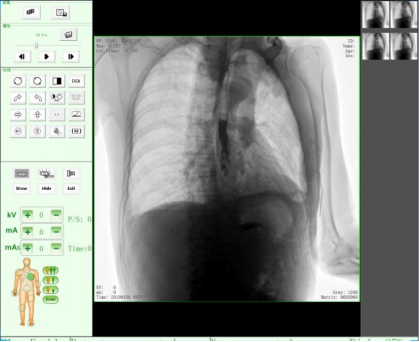

三、醫學用途,醫用X射線機作為醫學診斷重要的設備之一,目前市面上醫用X射線機種類主要有DR、CR、C形臂、乳腺機、胃腸機、口腔CBCT等醫療器械。設備依據X射線的穿透作用、差別吸收、感光作用和熒光作用,利用人體各組織的密度和厚度不同,通過檢測圖像陰影濃淡的對比,結合臨床表現、化驗結果和病理診斷,即可判斷人體某一部位/內部器官是否正常。此類X光機廣泛應用于醫療機構與場所,為相關單位提供了快速的醫療診斷。